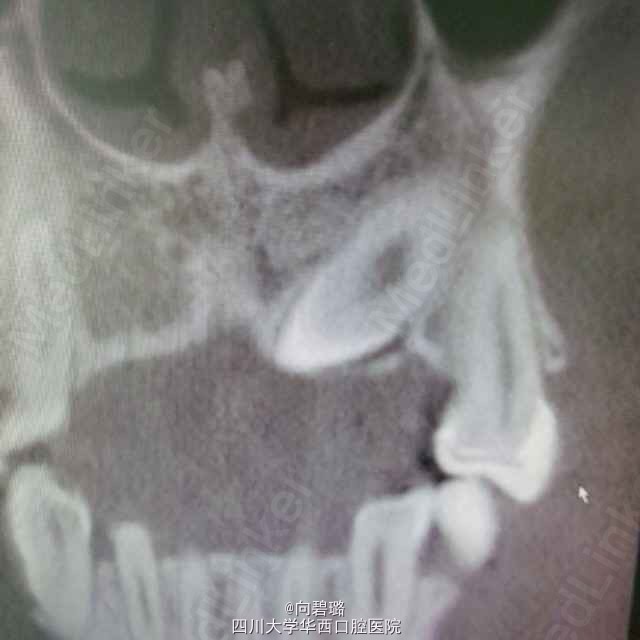

患者,男24岁左上颌乳牙滞留求治

63牙滞留,cbct示:23牙异位

23异位,拔除后行种植修复

尖牙异位还是比较常见的,我们定的方案是拔出后种植修复,不知道正畸能不能牵出?